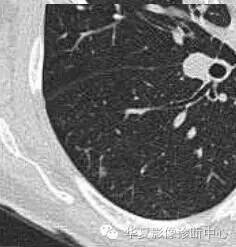

首先看边缘

是否清楚

这里是血管的边缘

病灶的边缘

GGO的边缘模糊,考虑炎性病变

如果不看边缘是否清楚,就好像癌肿

但是一看边缘就是炎性病变

大家记住了,边缘模糊的GGO首先考虑炎症